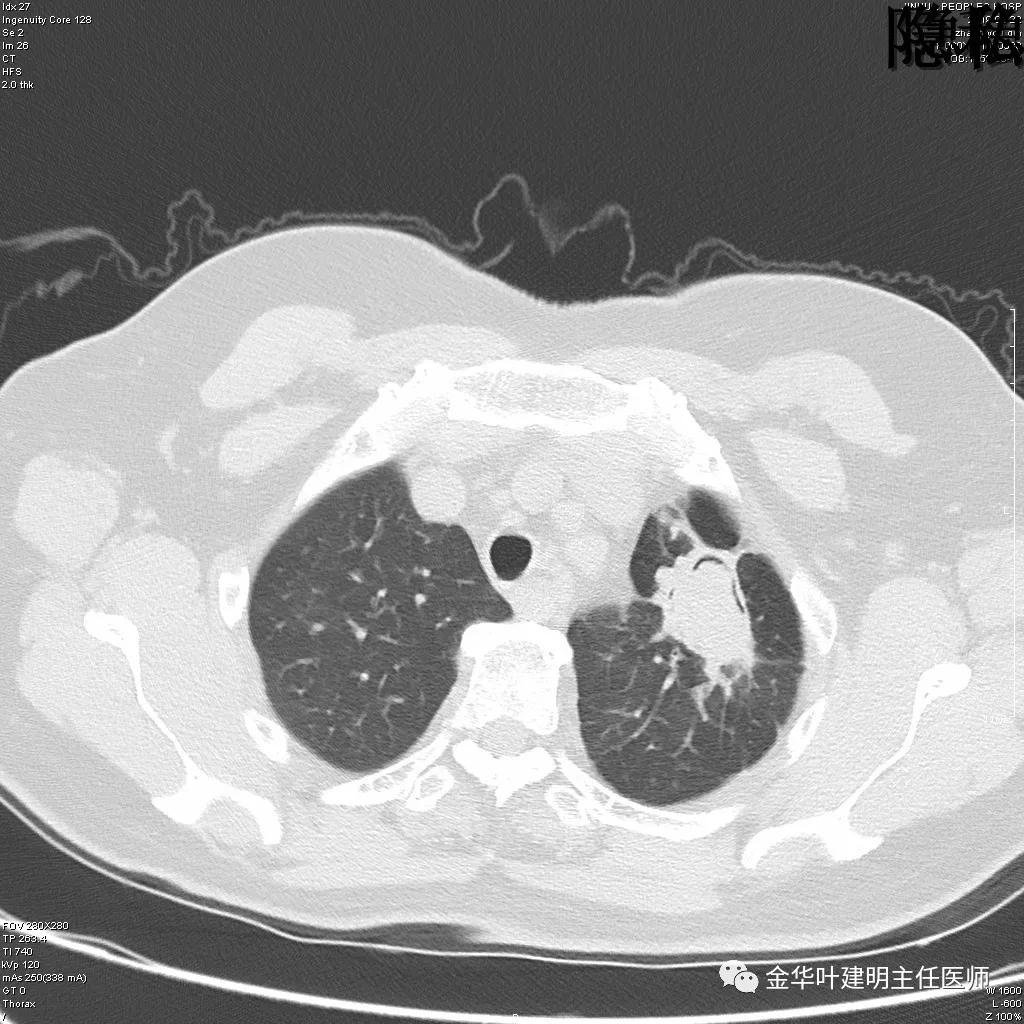

可见左肺下叶比较靠中央的部位也有一病灶,是混合磨玻璃影,偏实性,瘤肺边界清楚,是较为典型的肺癌表现。进一步的靶扫描图像如下:

靶扫描更清晰的显示细节,从影像上看,基本可以断定左下肺的是恶性肿瘤了,而且已经密度较高,长径也在3厘米以上,不能继续观察等待了!